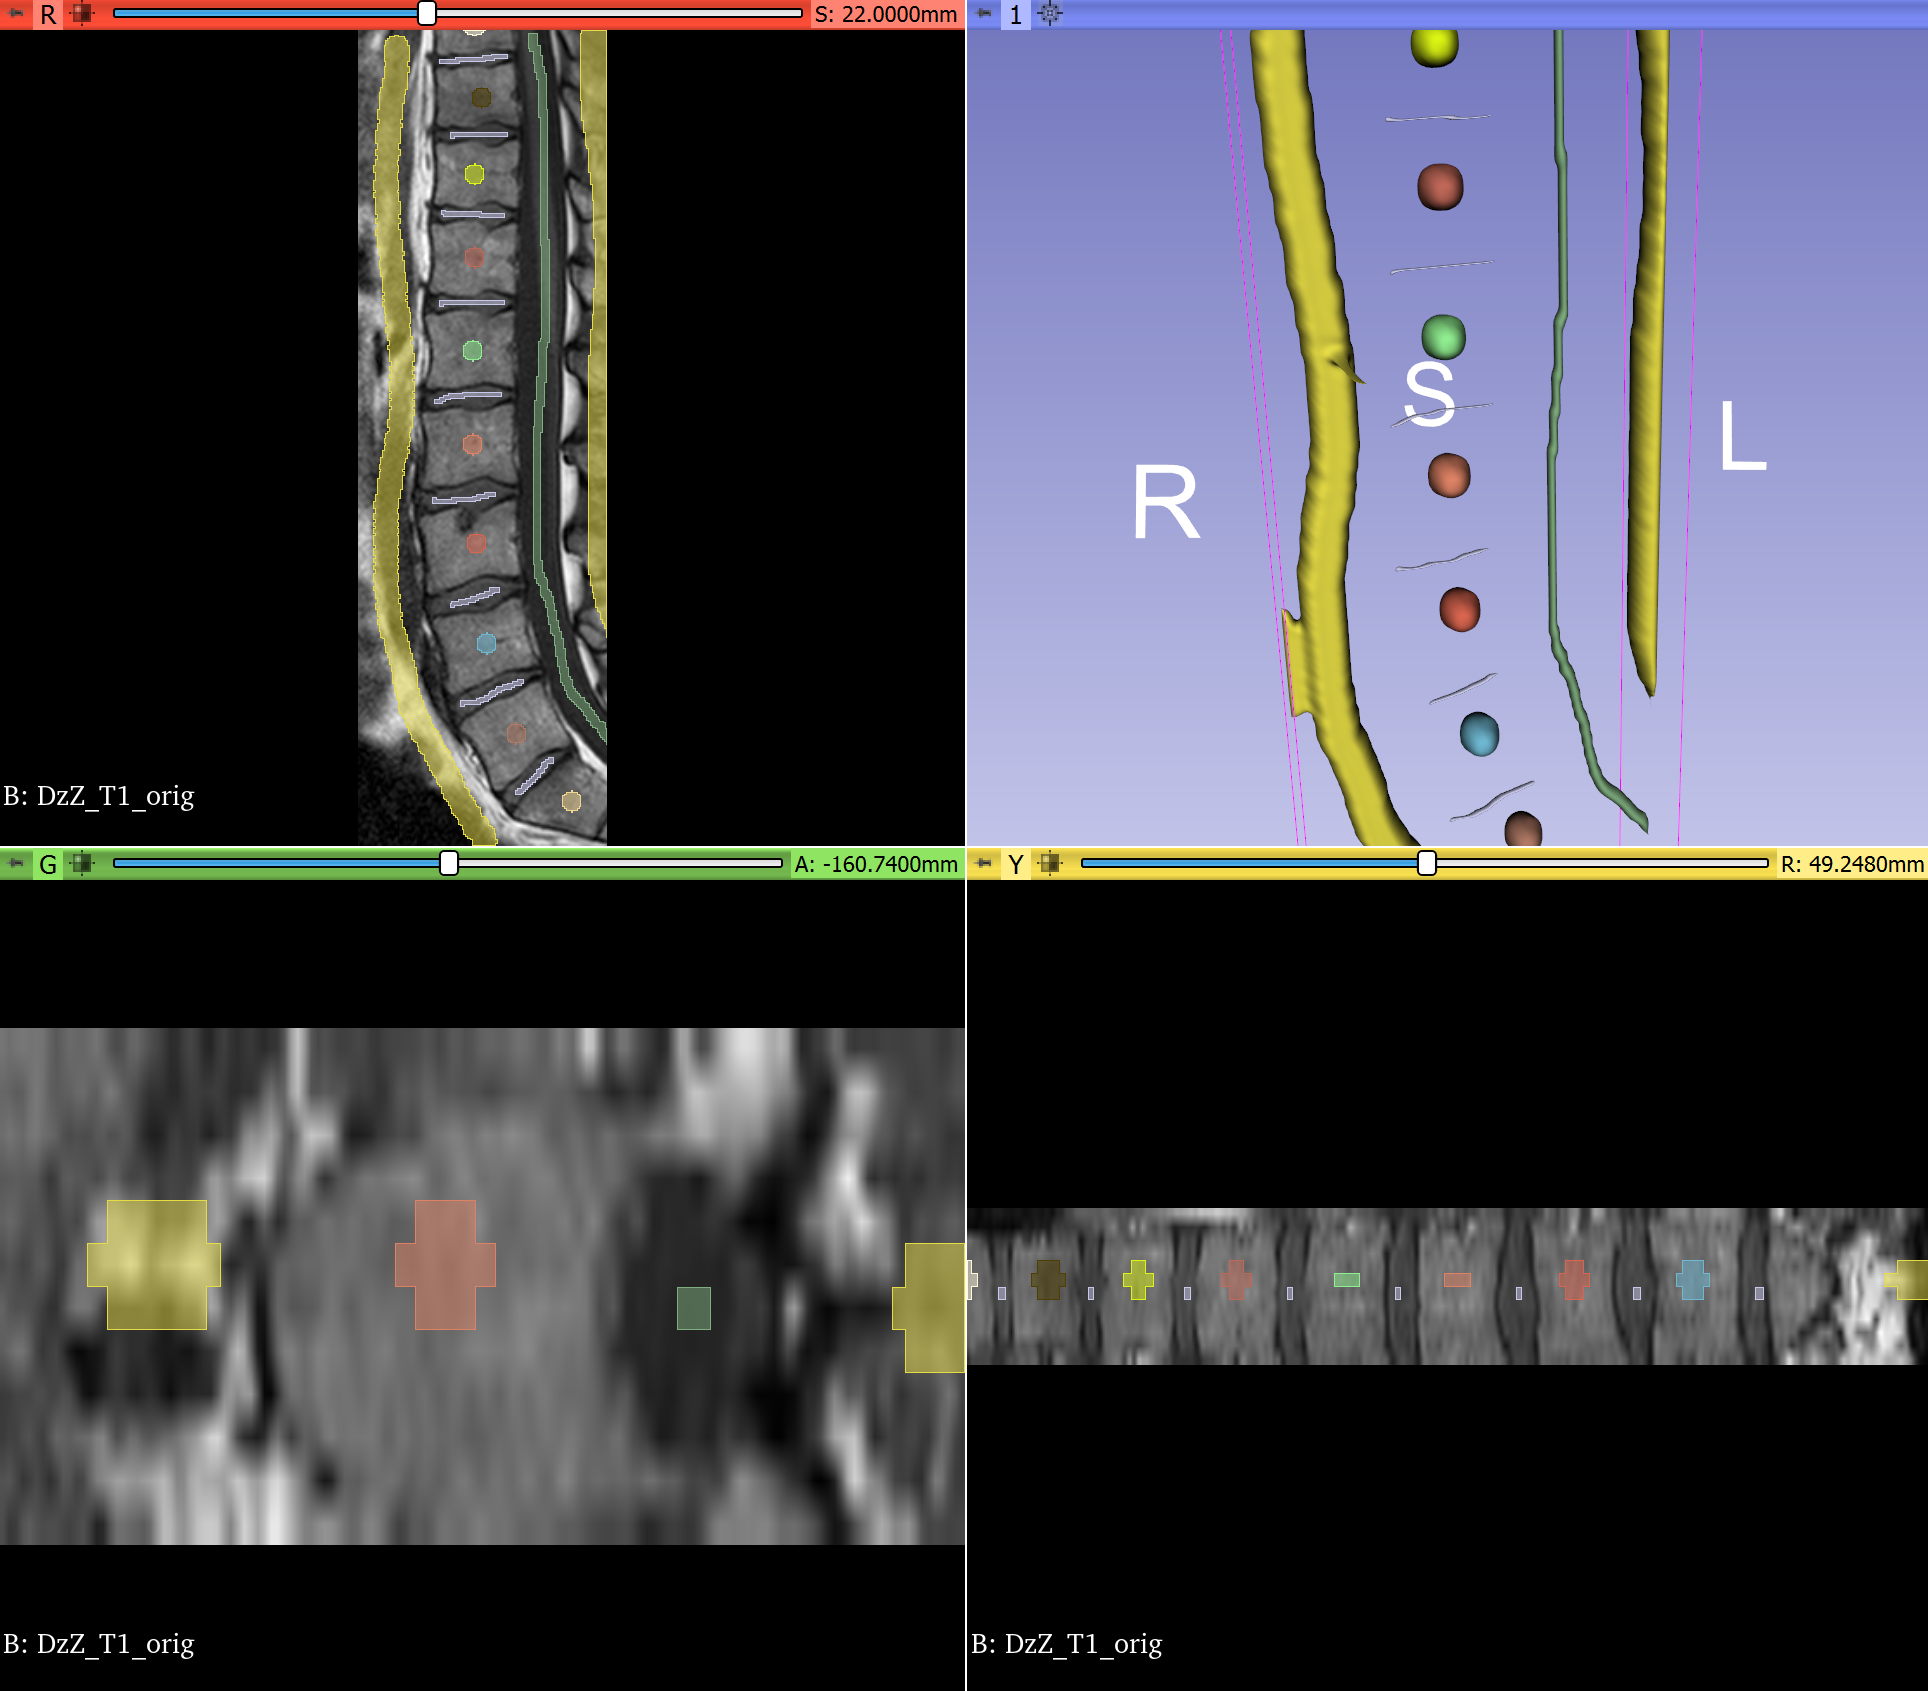

ITK 5.3 RC 4 highlights distributed computing support with Dask. Dask is a Python library that makes scaling analysis easy through simple programming on a laptop that can then be deployed to HPC or cloud computing resources. In ITK 5.3 RC 4, Dask support applied in medical imaging, bioimaging, and material science, is robust (caveat: import itk should be called in Dask worker functions). Furthermore, support was expanded from NumPy array views on itk.Image's to full metadata-preserving distributed computing with itk.Image, itk.Mesh, itk.PointSet, and itk.Transform. With ITK's Dask support, batch processing a cohort of thousands of medical images or processing biomicroscopy, histopathology, or geospatial images with trillions of pixels is now a matter of minutes instead of weeks.

Knee MRI mapping of cartilage thickness in osteoarthritis that leverages ITK's Dask support for distributed processing of large patient cohorts over the preprocessing, segmentation, registration, and post-processing steps of the analysis pipeline.